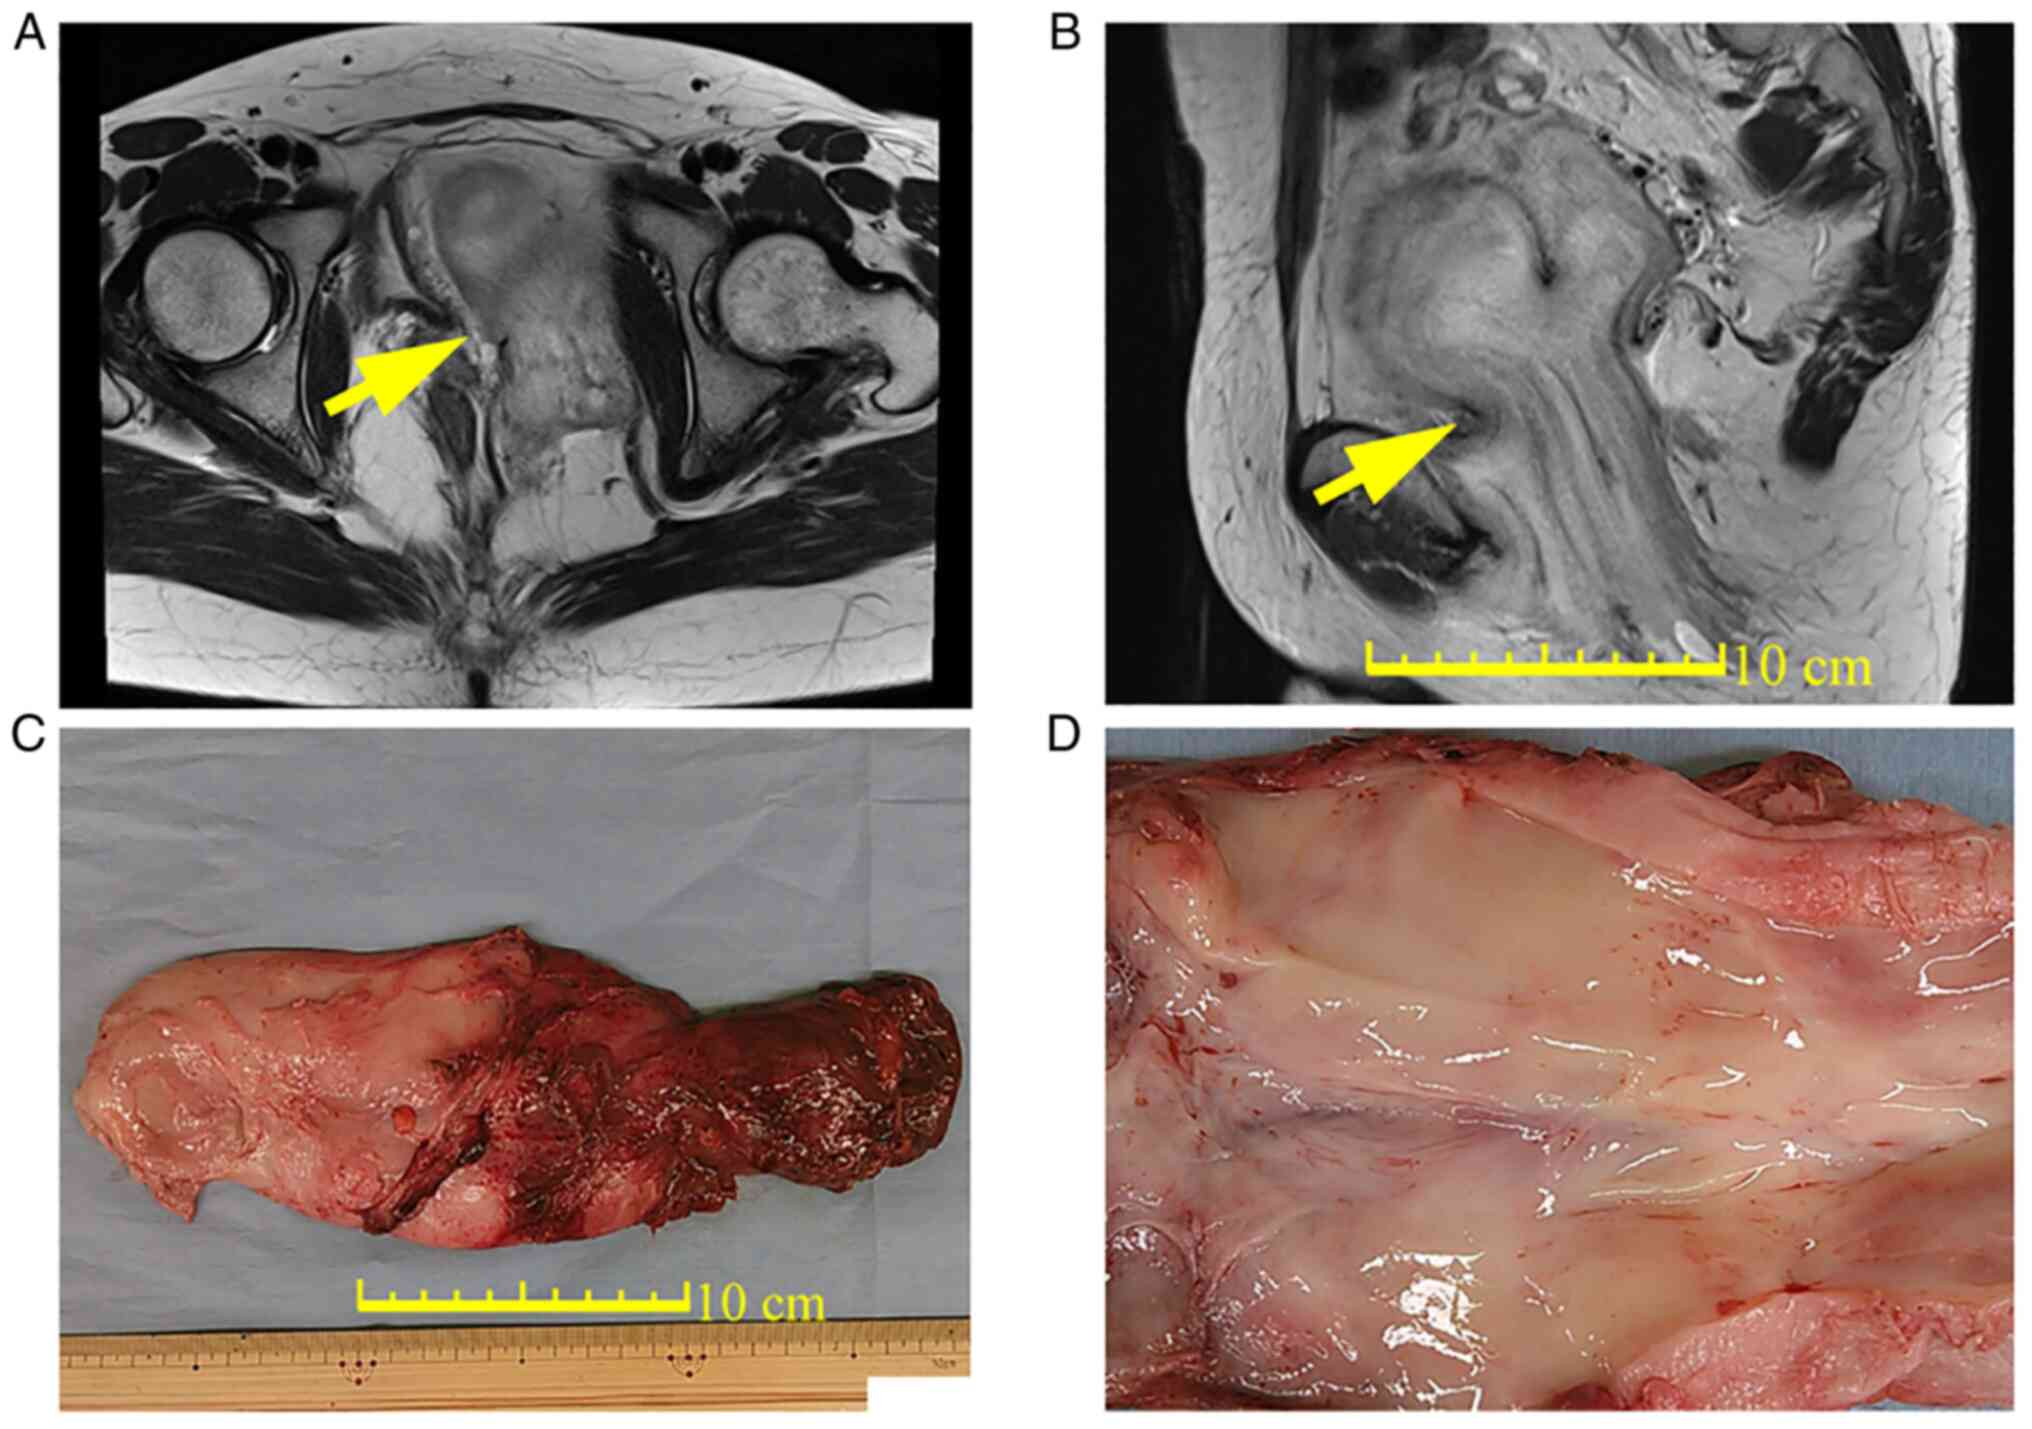

Prophylactic oophorectomy and aromatase inhibitors for premenopausal deep angiomyxoma: A case report and literature review

Deep angiomyxoma is a rare, infiltrative, hormone‑dependent, benign‑mesenchymal neoplasm that occurs in the deep soft tissues of the perineal regions. In total, 33% females with newly diagnosed deep angiomyxoma will typically relapse within 5 years after the standard treatment of radical resection. Postoperative hormone therapy is frequently administered to prevent recurrence, but the role of prophylactic oophorectomy in premenopausal women remain to be fully elucidated. In the present report, a 42‑year‑old Japanese woman was referred for a refractory Bartholin's cyst that is 14 cm in diameter. Based on the results of imaging (unenhanced CT and MRI) and histopathology, deep angiomyxoma was suspected, but no definitive diagnosis was possible. Tumor resection and bilateral salpingo‑oophorectomy were performed before the postoperative diagnosis was confirmed to be deep angiomyxoma. The patient received an aromatase inhibitor (2.5 mg letrozole daily) as adjuvant hormonal therapy. There was no evidence of recurrence at the 1‑year postoperative follow‑up. In conclusion, prophylactic oophorectomy and postoperative adjuvant therapy with aromatase inhibitors may be a promising treatment option for deep angiomyxoma to optimize the outcome of surgical treatment. Long‑term follow‑up is required to monitor for the late and/or local recurrence of deep angiomyxoma and possible adverse effects of adjuvant hormonal therapy.

Figure 1